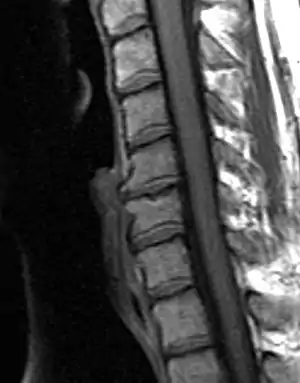

![]() | |

| Degenerated disc between C5 and C6 (vertebra at the top of the picture is C2), with osteophytes anteriorly (to the left) on the lower portion of the C5 and upper portion of the C6 vertebral body. | |